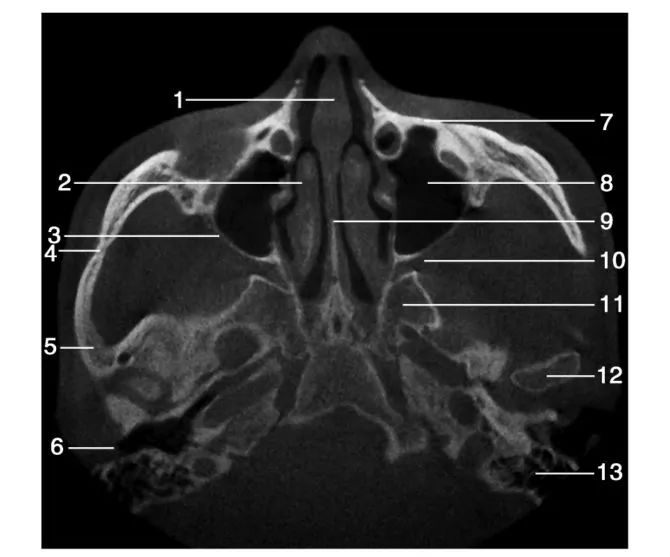

1.鼻中隔( nasal septum) ; 2.右侧中鼻甲( right middle nasal concha) ; 3.上颌窦后壁( posterior wall of maxillary sinus) ; 4.颧颞缝( zygomaticotemporal suture) ; 5.颞骨( temporal bone) ; 6.外耳道( external acoustic meatus) ; 7.上颌窦前壁( anterior wall of maxillary sinus) ; 8.左侧上颌窦( left maxillary sinus) ; 9.犁骨( vomer) ; 10.翼腭窝( pterygopalatina fossa) ; 11.翼突( pterygoid process) ; 12.下颌髁突( mandibular condyle) ; 13.乳突气房( mastoid cells)